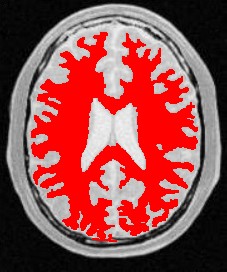

使用人体大脑截面图作为输入图像,选择合适的像素点作为种子像素,生长的结果如下图所示:

| 原始图像 | 连续阈值法 | 邻接连续阈值法 | 置信连接阈值法 |

| 参数 | [150,180] | [150,180] R:3 | Iter:10 factor:2.5 r:5 |

| 结果点数 | 15011 | 7854 | 14643 |